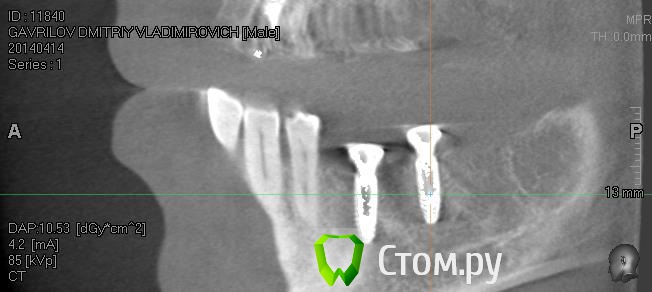

Driv Опубликовано 14 апреля, 2014 Автор Поделиться Опубликовано 14 апреля, 2014 Пойдет? Ссылка на комментарий

Bier Опубликовано 14 апреля, 2014 Поделиться Опубликовано 14 апреля, 2014 да, только надо и остальные 2 окошка тоже. наведите перекрестие на 1 и на другой имплантаты и дайте полную картинку экрана Ссылка на комментарий

Driv Опубликовано 14 апреля, 2014 Автор Поделиться Опубликовано 14 апреля, 2014 Так? Ссылка на комментарий

Bier Опубликовано 15 апреля, 2014 Поделиться Опубликовано 15 апреля, 2014 судя по этим срезам, все хорошо. 1 Ссылка на комментарий

IvanK Опубликовано 15 апреля, 2014 Поделиться Опубликовано 15 апреля, 2014 судя по этим срезам, все хорошо.Согласен Ссылка на комментарий